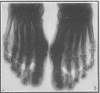

Congenital Familial Clubbing of the Fingers and Toes *